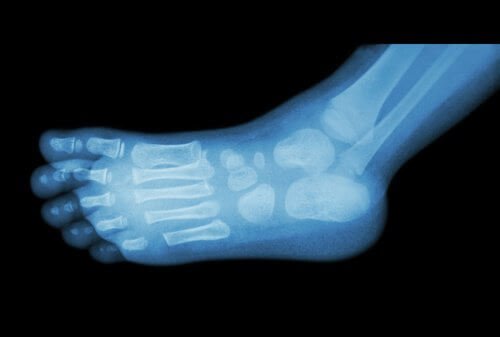

Per diagnosticare uno sperone è sufficiente una normale radiografia, anche se spesso è visibile a occhio nudo, dal momento che si tratta di una piccola protuberanza causata da un accumulo di calcio.